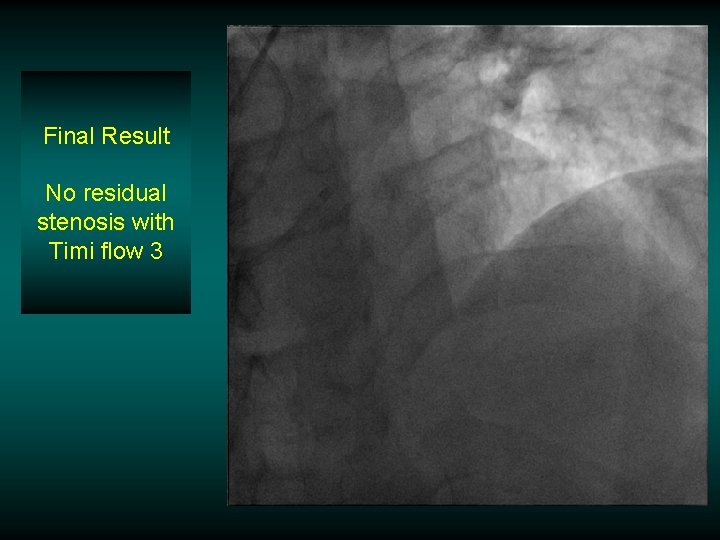

Final Result No residual stenosis with Timi flow 3